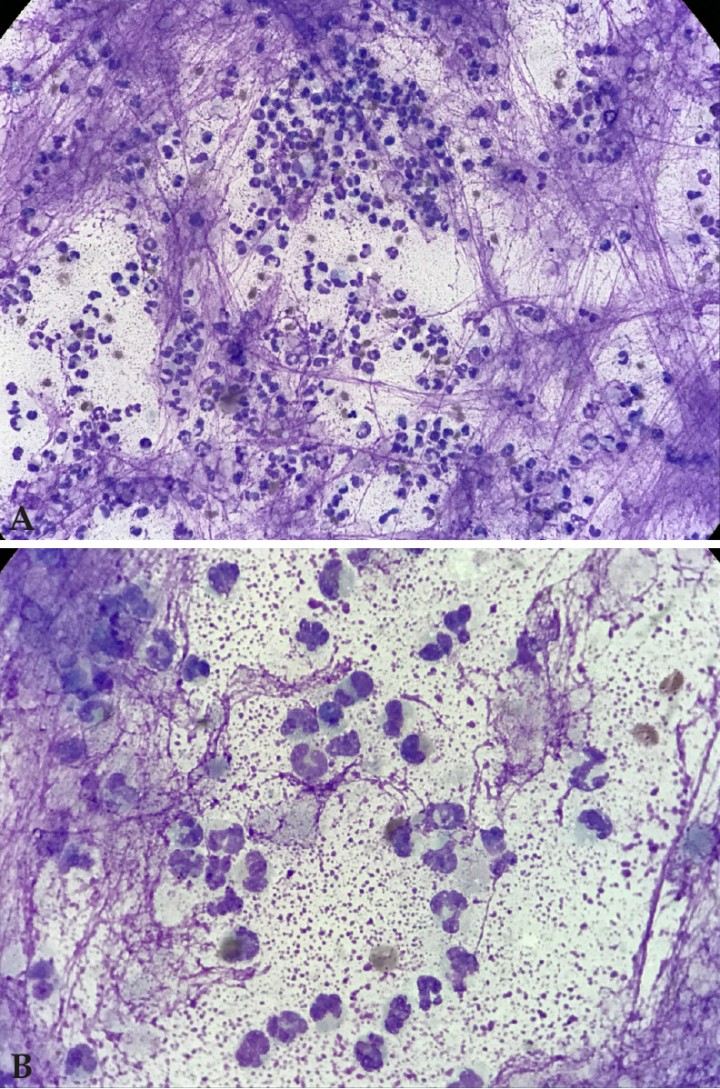

Tras conocer el origen en LN de la masa cervical, se realizó un estudio citológico, en el cual se observaron mayoritariamente neutrófilos (>90 %) y, raramente, macrófagos (<5 %), y se determinó la existencia de una linfadenitis neutrofílica, sin detectar microorganismos (Fig. 4). El cultivo bacteriano (aerobio y anaerobio) y fúngico del contenido del LN resultó negativo.

<p>(<strong>A</strong>) Microfotografía de extensión citológica de la masa submandibular, mostrando inflamación neutrofílica. (<strong>B</strong>) Se aprecian con mayor detalle numerosos neutrófilos degenerados. (Diff-Quik; objetivos de 40x y 100x).</p>

Figura 4

(A) Microfotografía de extensión citológica de la masa submandibular, mostrando inflamación neutrofílica. (B) Se aprecian con mayor detalle numerosos neutrófilos degenerados. (Diff-Quik; objetivos de 40x y 100x).